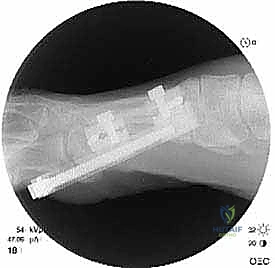

الخطوة الثالثة: قص العظم (Osteotomy)

باستخدام منشار جراحي ميكروسكوبي دقيق، يقوم الدكتور هطيف بقص عظم مشط القدم. تعتمد زاوية وشكل القص (مثل القص المائل أو القص على شكل حرف Z) على مقدار الإطالة المطلوبة وشكل العظم المتبقي من الجراحة السابقة.

الخطوة الرابعة: الإطالة والطعوم العظمية (Bone Grafting)

يتم إبعاد طرفي العظم المقصوص بلطف للوصول إلى الطول التشريحي المطلوب (والذي تم حسابه مسبقاً في صور الأشعة). لملء الفراغ الناتج عن الإطالة، يتم استخدام طعم عظمي (Bone Graft).

* الطعم الذاتي (Autograft): غالباً ما يتم أخذ قطعة صغيرة من العظم من كعب المريض (عظم العقب) أو من عظم الحوض، وهو الخيار الأفضل لأنه يحفز الالتئام السريع.

* الطعم الصناعي أو العظم البنكي (Allograft): يمكن استخدامه في بعض الحالات لتجنب إحداث جرح إضافي.

الخطوة الخامسة: التثبيت الداخلي القوي (Internal Fixation)

لضمان التئام العظم في وضعه الجديد والطويل، يجب تثبيته بقوة شديدة. يستخدم الدكتور هطيف أحدث الشرائح المعدنية التيتانيوم ذات الزاوية الثابتة (Locking Plates) والمسامير الدقيقة. هذا التثبيت القوي يمنع أي حركة بين العظام ويسمح ببدء العلاج الطبيعي في وقت مبكر.